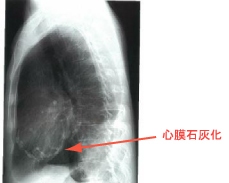

<胸部X線写真>

心膜石灰化の所見がみられます。また、心タンポナーデ同様、肺血流も低下するために肺野は明るく見えます。